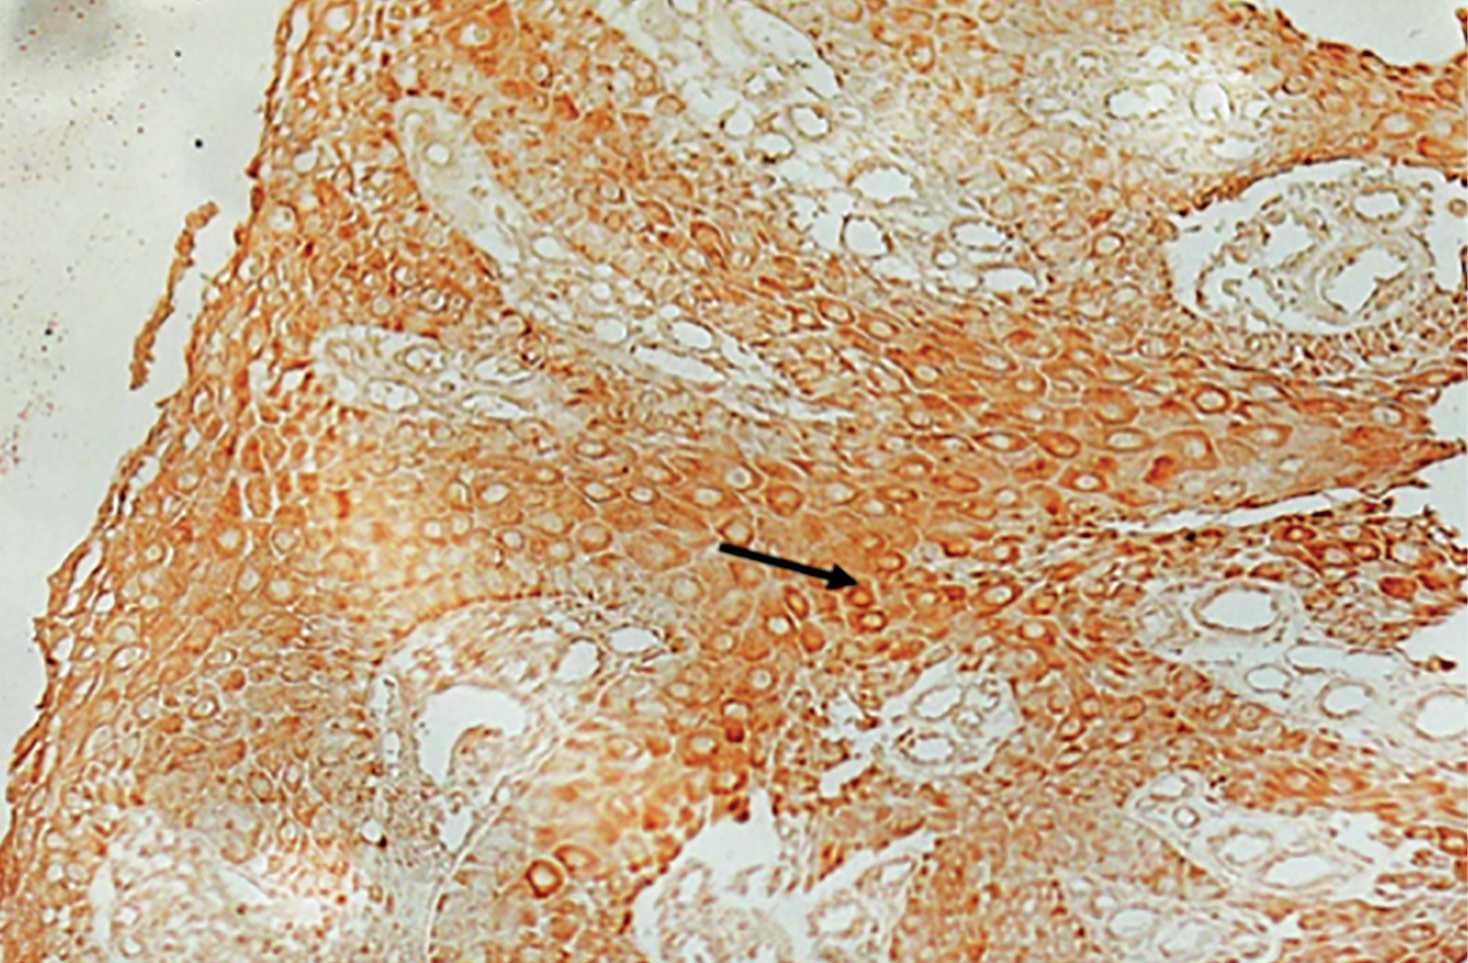

На момент включения пациентов с СД нейропатические раны имели утолщенный роговой слой, митотически активные клетки локализовались во всех слоях эпидермиса, включая слои с дифференцированными клетками, зернистый слой практически отсутствовал, кератиноциты рогового слоя сохраняли ядра (паракератоз) (рис. 2) по сравнению с кожей больных с пролежнями, строение эпидермиса которых не отличалось от здоровой кожи (по литературным данным).

Рисунок 2. Гистологическая картина кожи пациента

с нейропатической раной стопы (а, b, c)

и участки пролежня пояснично-крестцового отдела (d).

Окраска. Стрелками указаны митотически активные клетки.